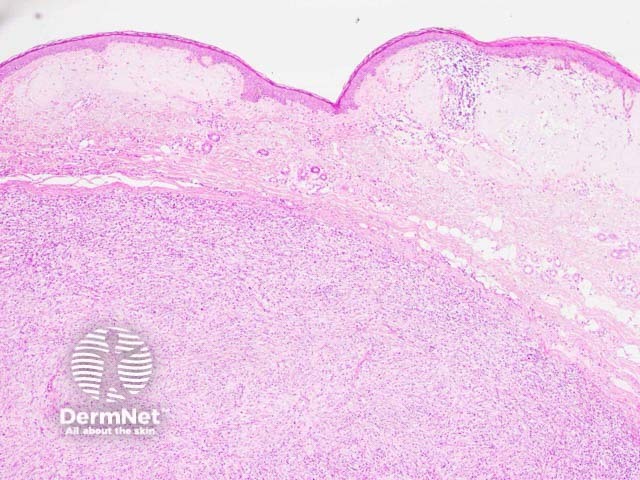

Histologically, the lesion is based in the dermis and seen underlying a normal epidermis (figure 1). The tumour is composed of an admixture of spindle-shaped and ovoid cells with a prominent inflammatory infiltrate (figures 2–3). The infiltrate is characteristically rich in plasma cells (best seen in figure 2). There may be some pleomorphism of the tumour cells and some mitotic figures (figure 3, arrow).

Figure 1